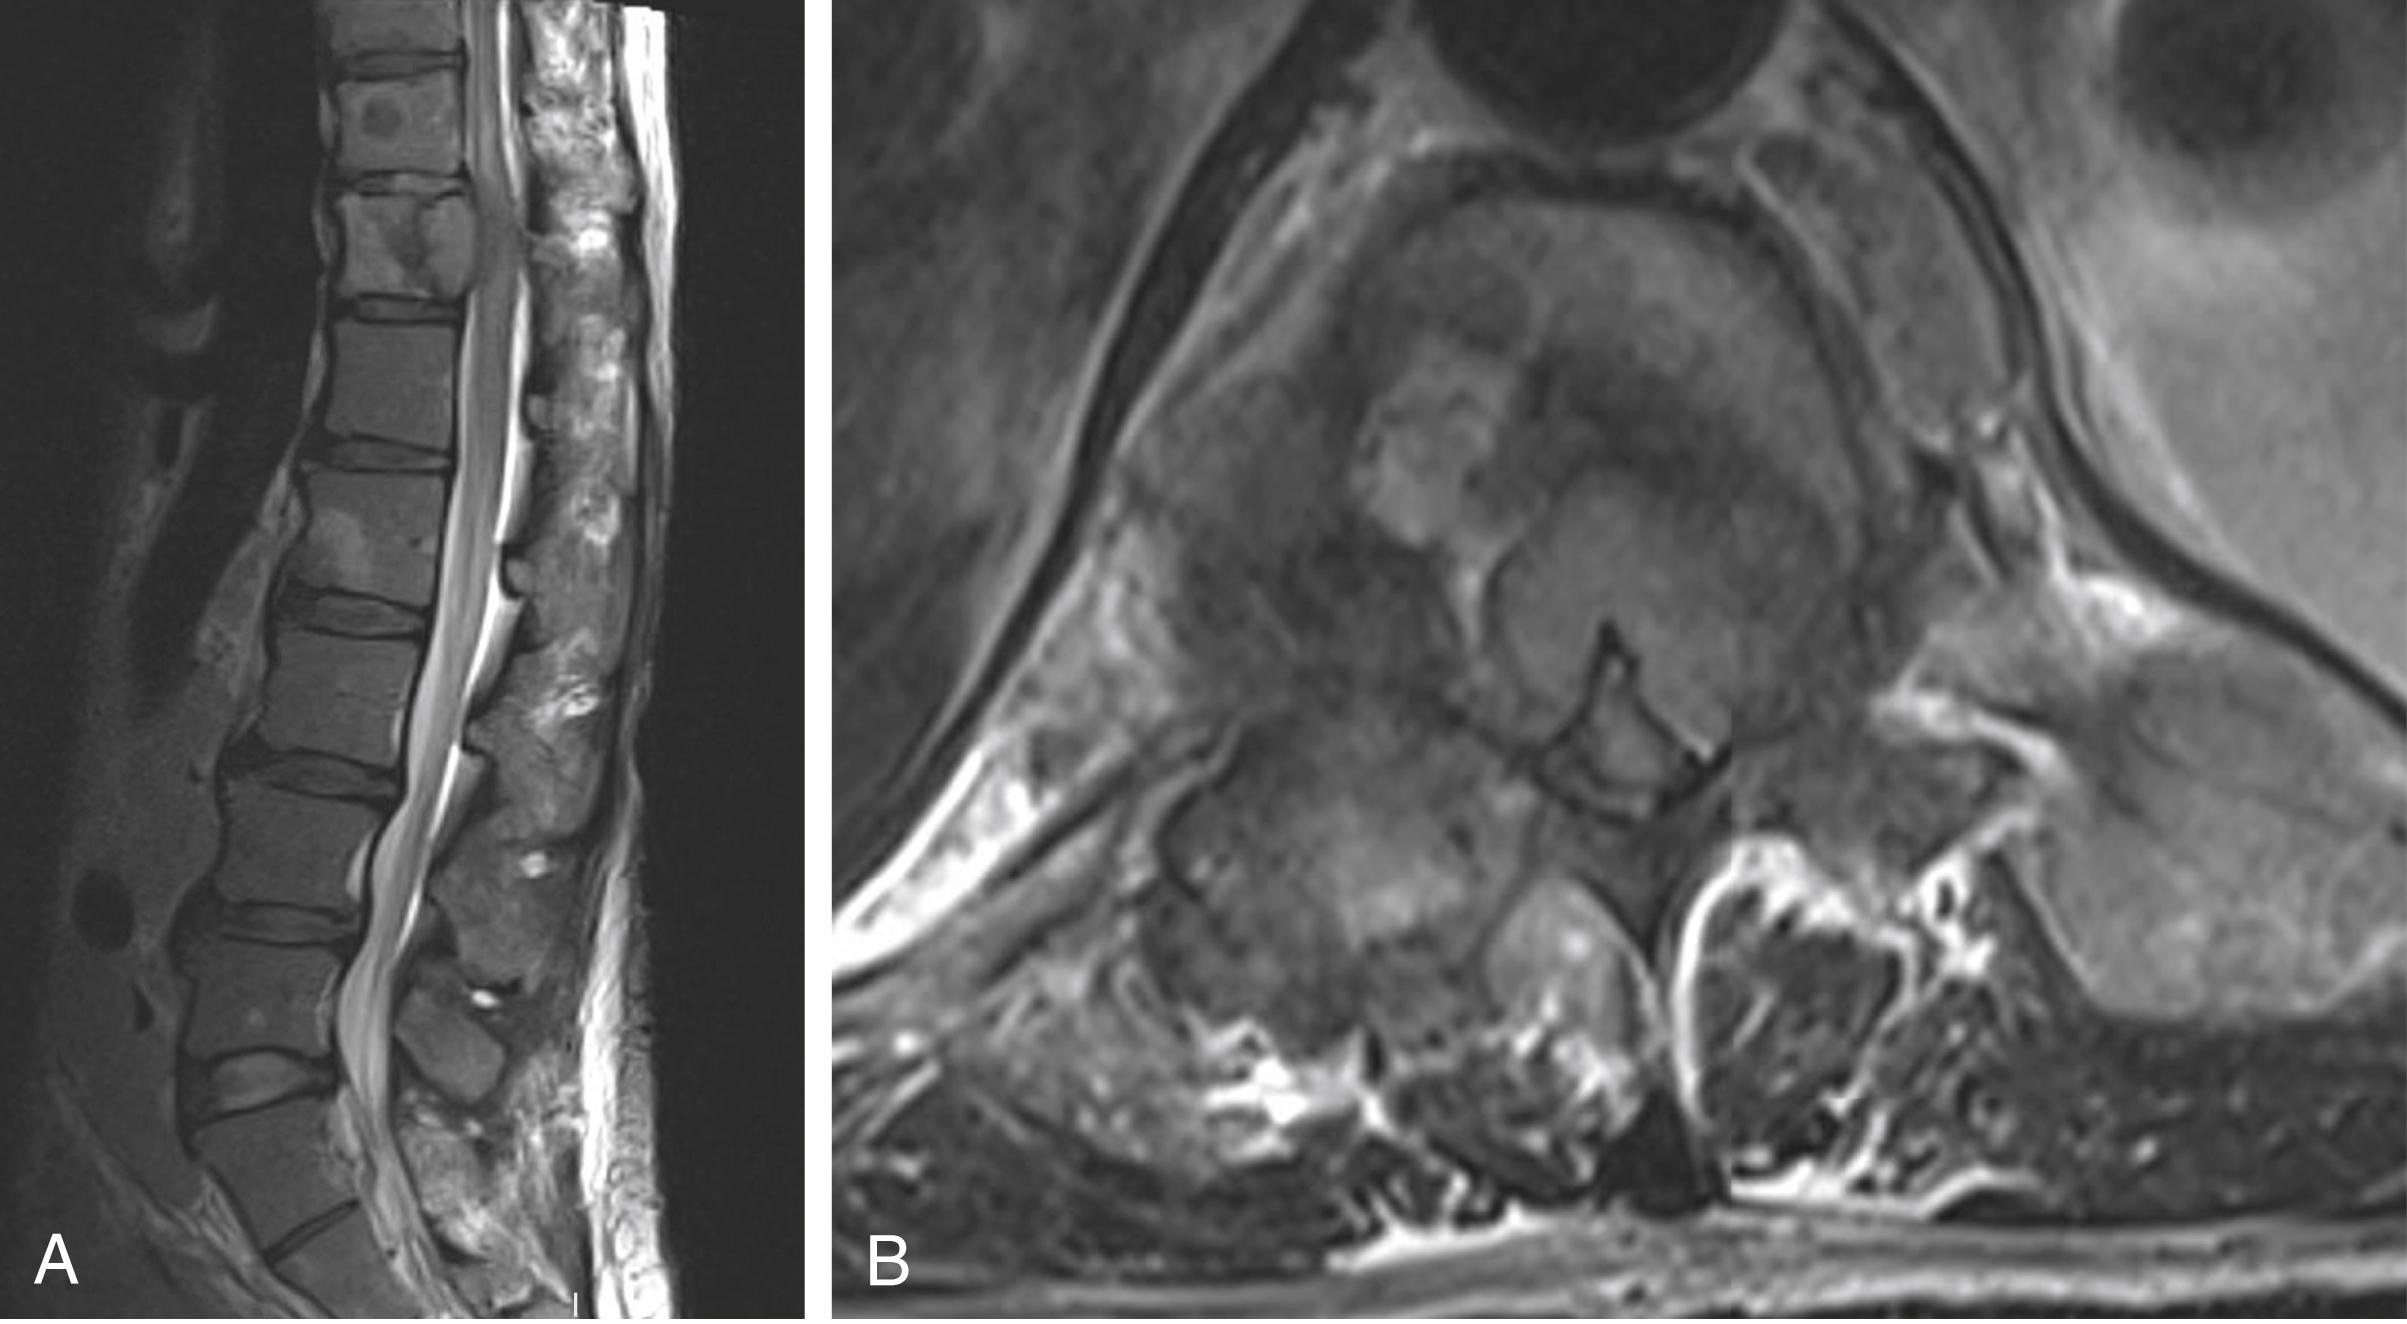

Fig. 42.2, A. Sagittal T2-weighted MRI of the thoracolumbar spine without contrast demonstrates an expansile lesion at T12 with posterior epidural extension. There is cord signal change at T11-T12 and multiple intraosseous lesions throughout the thoracolumbar spine. B. An axial sequence at T11-T12 demonstrates circumferential epidural cord compression with no evidence of CSF surrounding the cord.